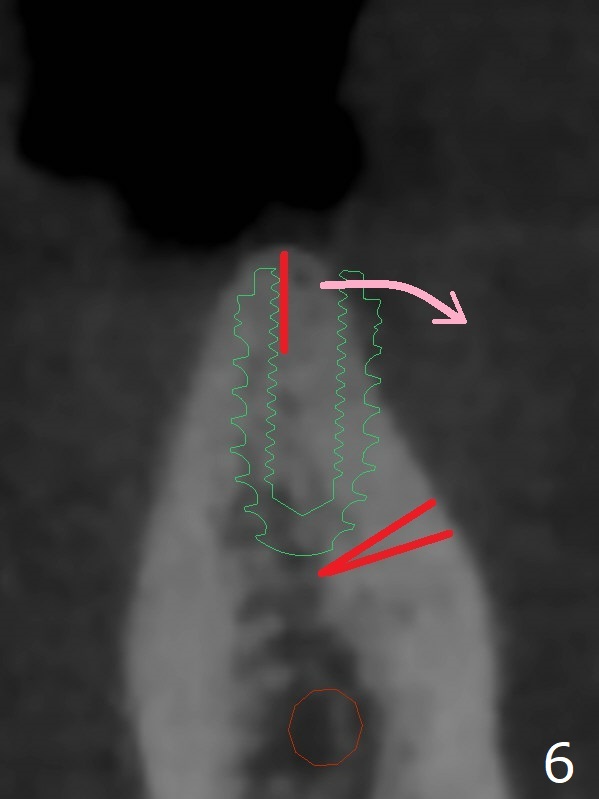

When implants at #4, 13 and 14 are placed, the patient wonders how many more implants are needed. From 0 (considering a lower RPD) to 5 (#3, 19, 20, 25 and 30). The tooth #3 seems to have periodontal-endodontic disease (Fig.1,2). Since the ridge is narrow at #19 and 20 (Fig.3), ridge split at #19 and a 1-piece implant at #20 are planned (Fig.4,5-9). The implant at #19 will be placed in an ideal prosthetic position (Fig.5). The ridge transverse bony cut will be made free hand in the middle (Fig.6,6'), followed by 2 vertical cuts and 1 apical transverse one in the 1st stage of procedure. In order to rotate the buccal block easier (Fig.6 pink curved arrow), the apical transverse cut will be wedge in shape (Fig.6 (red), 6' (double lines), 7 (black)). In the 2nd stage, the ridge top split will be extended by using a chisel (Fig.7 longer red line) and the buccal block will be pushed buccally (Fig.8). A guide will be seated to finish osteotomy (Fig.9 white) and implant placement.